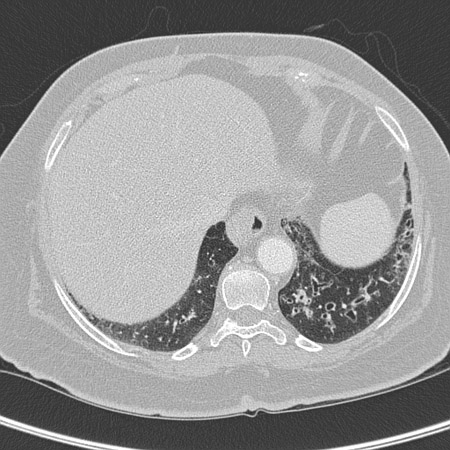

Exploración por TC de tórax de un paciente con toxicidad pulmonar por amiodarona, que muestra opacidades asimétricas con una distribución periférica

De la colección personal del Dr. A. Pataka y el Profesor P. Argyropoulou, Aristotle University, Thessaloniki, Grecia